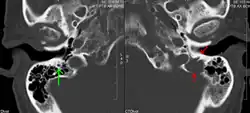

Medical imaging

The diagnostic examination of a person with suspected multiple myeloma typically includes a skeletal survey. This is a series of X-rays of the skull, axial skeleton, and proximal long bones. Myeloma activity sometimes appears as "lytic lesions" (with local disappearance of normal bone due to resorption) or as "punched-out lesions" on the skull X-ray ("raindrop skull"). Lesions may also be sclerotic, which is seen as radiodense.[76] Overall, the radiodensity of myeloma is between −30 and 120 Hounsfield units (HU).[77] Magnetic resonance imaging is more sensitive than simple X-rays in the detection of lytic lesions. An MRI may supersede a skeletal survey, especially when vertebral disease is suspected. Occasionally, a CT scan is performed to measure the size of soft-tissue plasmacytomas. Nuclear Medicine Bone scans are typically not of any additional value in the workup of people with myeloma (no new bone formation; lytic lesions not well visualized on nuclear bone scan).